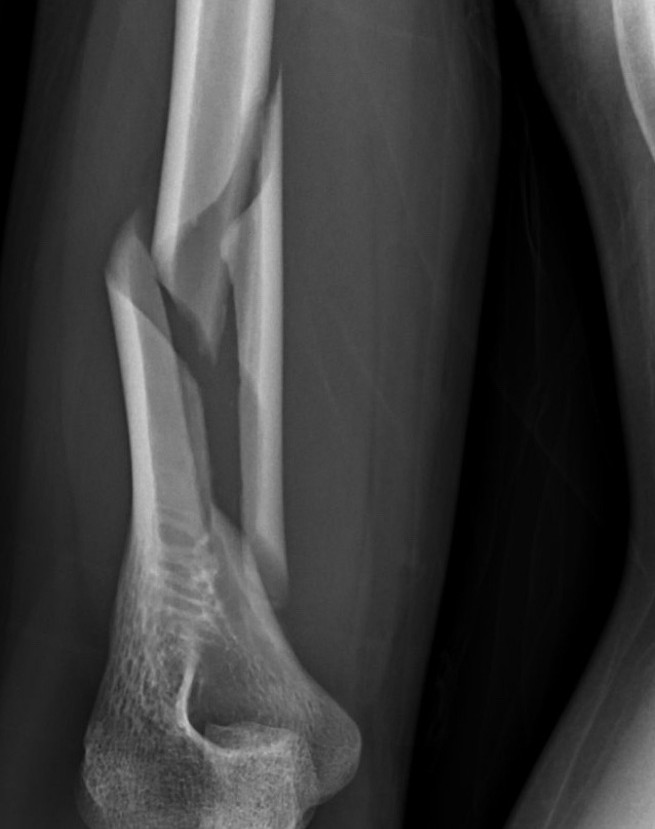

一名29歲男子與友人比腕力時,因瞬間扭轉力過大,導致右上臂肱骨當場發生「螺旋性骨折」。花蓮慈濟醫院骨科醫師張家銘指出,這類骨折與跌倒撞擊不同,主要是因為比腕力時手臂形成槓桿,力量集中在肱骨遠端,當旋轉扭力超過骨頭負荷,骨頭就會像被擰斷一樣破碎。醫師特別提醒,肱骨附近有重要的橈神經通過,一旦骨折波及神經,可能導致手腕與手指無法伸直的「垂腕」症狀,嚴重影響日常生活。

針對此個案,醫療團隊採取手術復位,在保護神經的前提下利用鋼板固定,協助骨頭穩定癒合。張家銘醫師進一步指出,這類骨折常見於年輕族群,特別是手臂較長、四肢纖細、身材瘦高者,主因是手臂越長產生的力矩越大,瞬間內旋的壓力極易摧毀骨質。